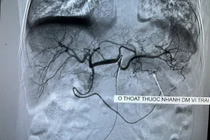

Với người bệnh cao tuổi, thể trạng gầy yếu, không đảm bảo sức khoẻ, thì phương pháp nút mạch cầm máu tiêu hoá với nhiều ưu điểm là lựa chọn tốt nhất.

Với phương pháp nút mạch cầm máu cấp cứu, các bác sĩ Bệnh viện Đa khoa tỉnh Lạng Sơn đã cấp cứu thành công bệnh nhân 66 tuổi chảy máu từ dạ dày.

Ổ chảy máu trên màn hình - Ảnh BVCC